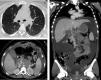

2ImagingRepresentative imaging studies of the lesions are presented. The axial cuts and lung window of the chest CT shows the lungs from the apices to the bases, with multiple nodular subpleural and pulmonary lesions, which are small but visible. Moreover, there is a left laminar pleural effusion (Fig. 1A). At the abdominal level, the intravenous contrast enhanced CT scan showed a lesion of irregular borders in the omental transcavity, partially defined, with loss of interface with the gastric wall, the anterior wall of the pancreas, and duodenum, which made impossible to determine the origin of the lesion (Fig. 1B). Vascular structures could not be adequately observed; the portal vein and the celiac trunk were compromised. Multiple nodular lesions were observed in the greater omentum. In the following CT cuts, multiple nodular lesions in the liver parenchyma with a discrete enhancement after contrast administration were observed (Fig. 1C). A follow-up triphasic CT scan (arterial, venous, and equilibrium phases) was ordered. In the venous phase, multiple nodular lesions adjacent to the pancreas were present (Fig. 2A). A diffuse gastric wall thickening and persistent ascites were noticed (Fig. 2B). In the last CT scan, seven months later, the subpleural lesions had increased in size and number. Notably, there were no observable lesions in the lung parenchyma. The liver lesions persisted (Fig. 2C).

A. Peripheral pulmonary lesions are shown. B. Multiple nodular lesions enhanced with the administration of contrast located to the major omentum and a great quantity of peritoneal fluid are observed. C. This coronal plane shows the extension of the fluid present that provoked the centralization of the intestinal loops.

A. The vascular structures keep their morphology. In both the venous and arterial phases it is observed that the celiac trunk as well as the portal vein are not adequately defined. B. Liver nodular lesions persist. C. The peritoneal nodular lesions have increased and the volume of the ascitic fluid previously observed has decreased.

Considering the three CT scans, a diagnosis of a probable neoplastic lesion in the omental transcavity, probably of gastric or pancreatic origin, with secondary hepatic and peritoneal deposits, ascites, and lung atelectasis was integrated.